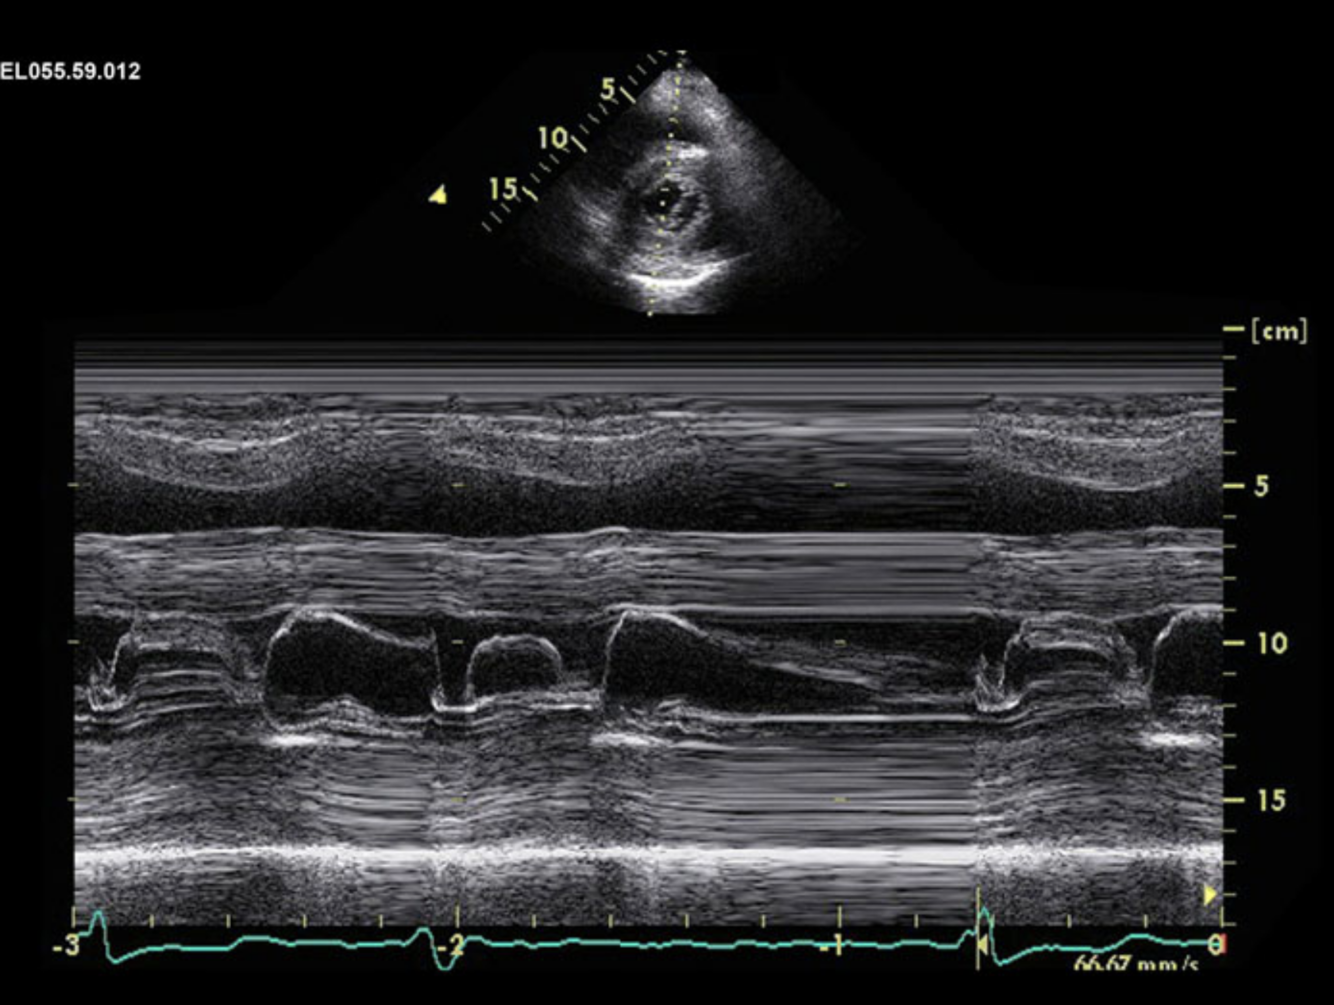

Describe the findings of M mode: